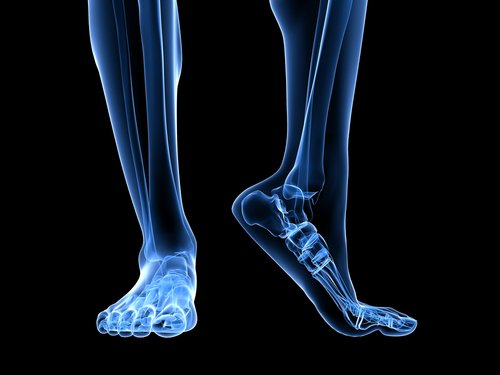

Anatomia del piede

Sono diverse le strutture anatomiche che permettono la flessione plantare e che possono, quindi, provocare il sovraccarico della fascia plantare.

Il tendine d’Achille è un legamento che va dal muscolo gastrocnemio (o muscoli gemelli) e dal soleo fino al calcagno. La contrazione del tendine di Achille provoca un aumento di pressione sul calcagno e, successivamente, un aumento di pressione sul legamento arcuato.

Un altro fattore anatomico da considerare è l’appoggio del piede, ossia il modo in cui il piede poggia a terra. I piedi piatti o la tendenza pronatoria provocano un maggiore stiramento della fascia plantare aumentando il rischio di lacerazione del tessuto a causa della maggiore pressione esercitata.